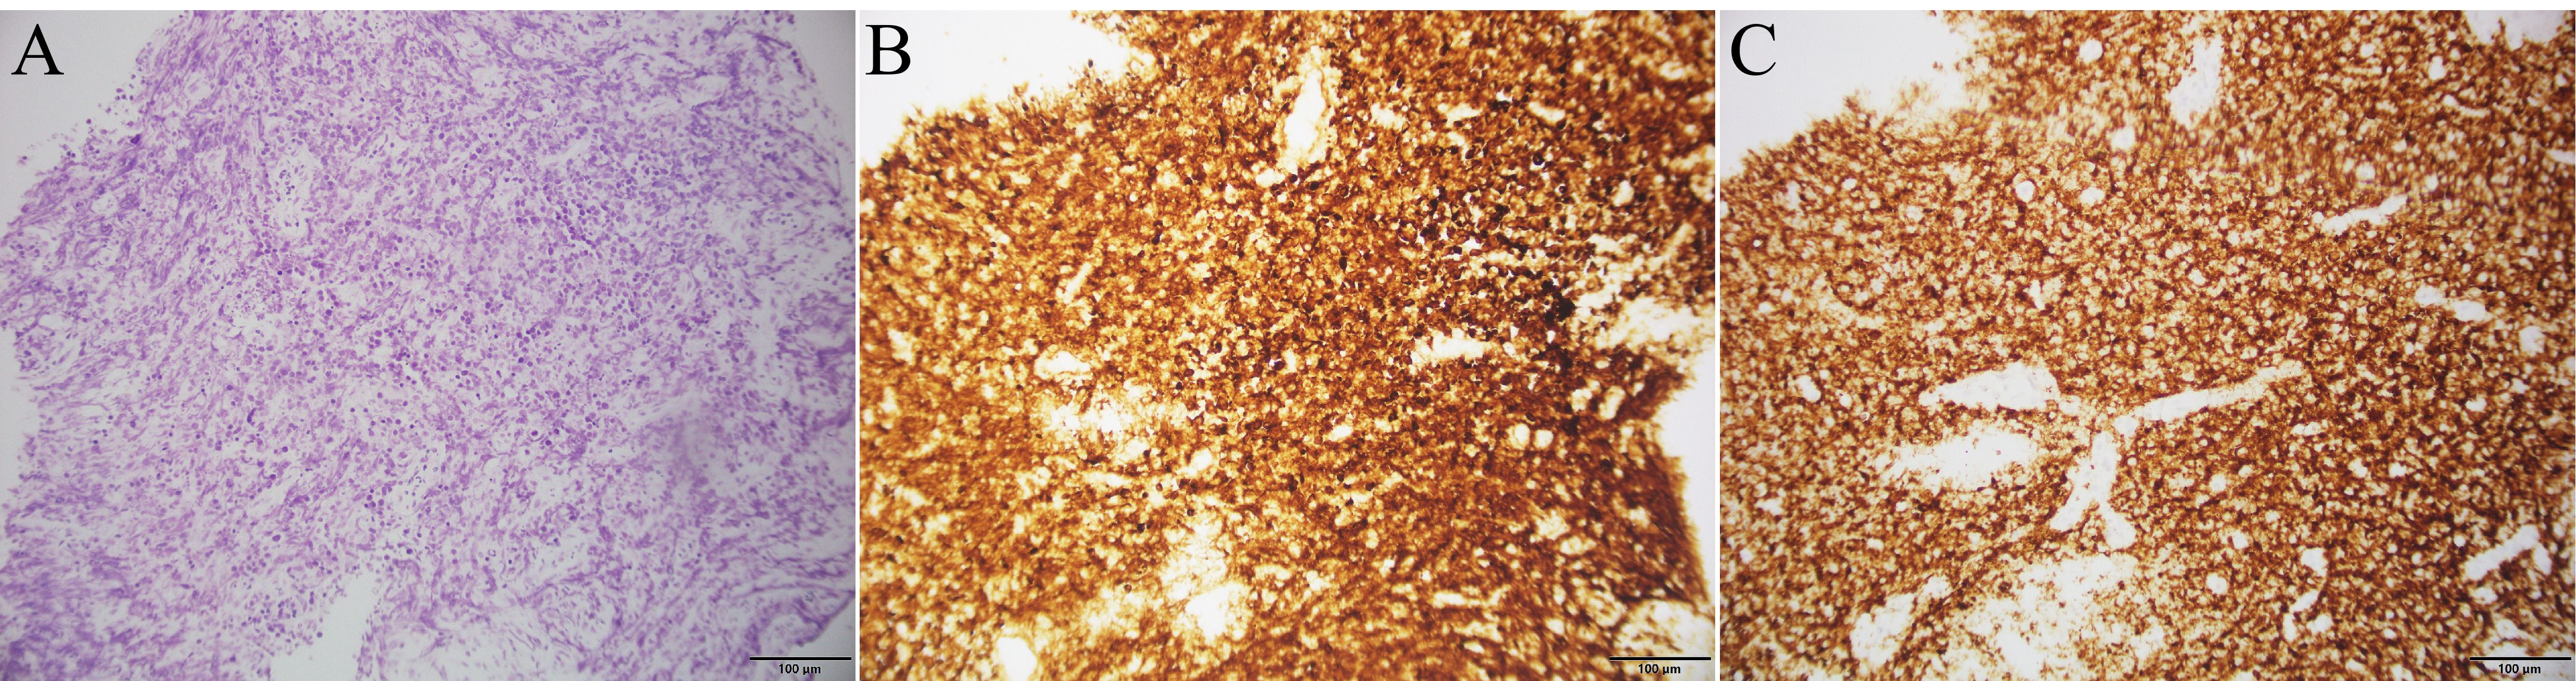

A 78-year-old male presented with abdominal pain and underwent contrast-enhanced CT at an outside hospital, which revealed a large hepatic mass with internal hemorrhage and significant thickening of the ileal wall, both highly suspicious for malignancy. The patient exhibited no B symptoms such as fever, night sweats, or weight loss, and routine laboratory tests, including blood counts, liver and renal function, electrolytes, and tumor markers, were unremarkable. The patient had no significant past medical history and no family history of malignancy. The patient initially received interventional treatment to control hepatic bleeding. After achieving hemodynamic stabilization, an ileal biopsy was performed via colonoscopy, and pathological examination confirmed the diagnosis of diffuse large B-cell lymphoma (Figure 1A). Immunohistochemical staining (Figures 1B, C) showed the following profile: CD20(+), CD79α(+), CD3 (scattered+), CD45RO (scattered+), CD5 (scattered+), CD23(−), Bcl-2 (90%+), Bcl-6 (90%+), C-MYC (50%+), CD10 (+), MUM-1(+), CD56(−), TIA-1(−), P-CK(−), and Ki-67 (90%+). Immunohistochemical analysis revealed positivity for CD20 and CD79α, confirming B-cell lineage. High expression levels of Bcl-2, Bcl-6, and C-MYC, along with a Ki-67 index of 90%, indicated high tumor aggressiveness. The CD10(+)/MUM-1(+) profile suggested a germinal center B-cell (GCB) subtype, supporting the histopathological diagnosis of DLBCL. For disease staging, the patient was referred to our hospital for [18F]FDG PET/CT. [18F]FDG was administered intravenously at a dose of approximately 5.5 MBq/kg, and imaging was performed using a United Imaging uMI 550 PET/CT system. PET/CT (Figures 2A–J) revealed markedly increased FDG uptake in both hepatic and ileal lesions. Additionally, PET/CT identified a slightly hyperdense nodule in the right kidney—missed on prior CT—with significantly elevated FDG metabolism. The patient underwent biopsies of both the liver and kidney lesions at another hospital prior to receiving further treatment, and the pathological results confirmed the diagnosis of lymphoma. This effectively ruled out the possibility of multiple primary malignancies.The final stage of lymphoma was determined to be stage IV, with an International Prognostic Index(IPI) score of 3. Three months later, the patient completed four cycles of R-CHOP chemotherapy. Follow-up [18F]FDG PET/CT (Figures 3A–J) demonstrated significant reduction in the size of hepatic, ileal, and renal lesions with markedly decreased FDG metabolism, indicating an excellent treatment response. The patient's disease timeline is shown in Table 2.

Figure 1

Three microscopic images labeled A, B, and C showing tissue samples. Image A shows a H&E stained section with light purple hues indicating cell nuclei. Images B and C depict brown immunohistochemistry stained tissue, highlighting protein expression with denser staining in Image C compared to Image B. Scale bars show 100 micrometers.

Figure 1. Histopathological and immunohistochemical findings of ileal biopsy: (A) Histopathological image of ileal tissue stained with hematoxylin and eosin; (B) Immunohistochemical image of Bcl-2; (C) Immunohistochemical image of CD20.